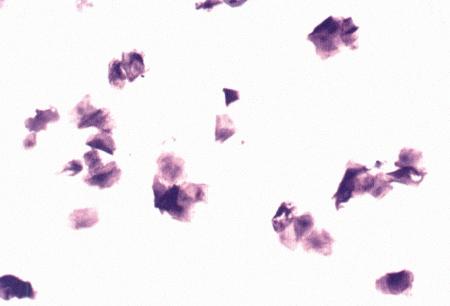

Фиг. 3.4.

Поверхностные клетки в мазке вагинальных выделений у суки в период эструса (окрашивание мазка Schorr's trichrome).